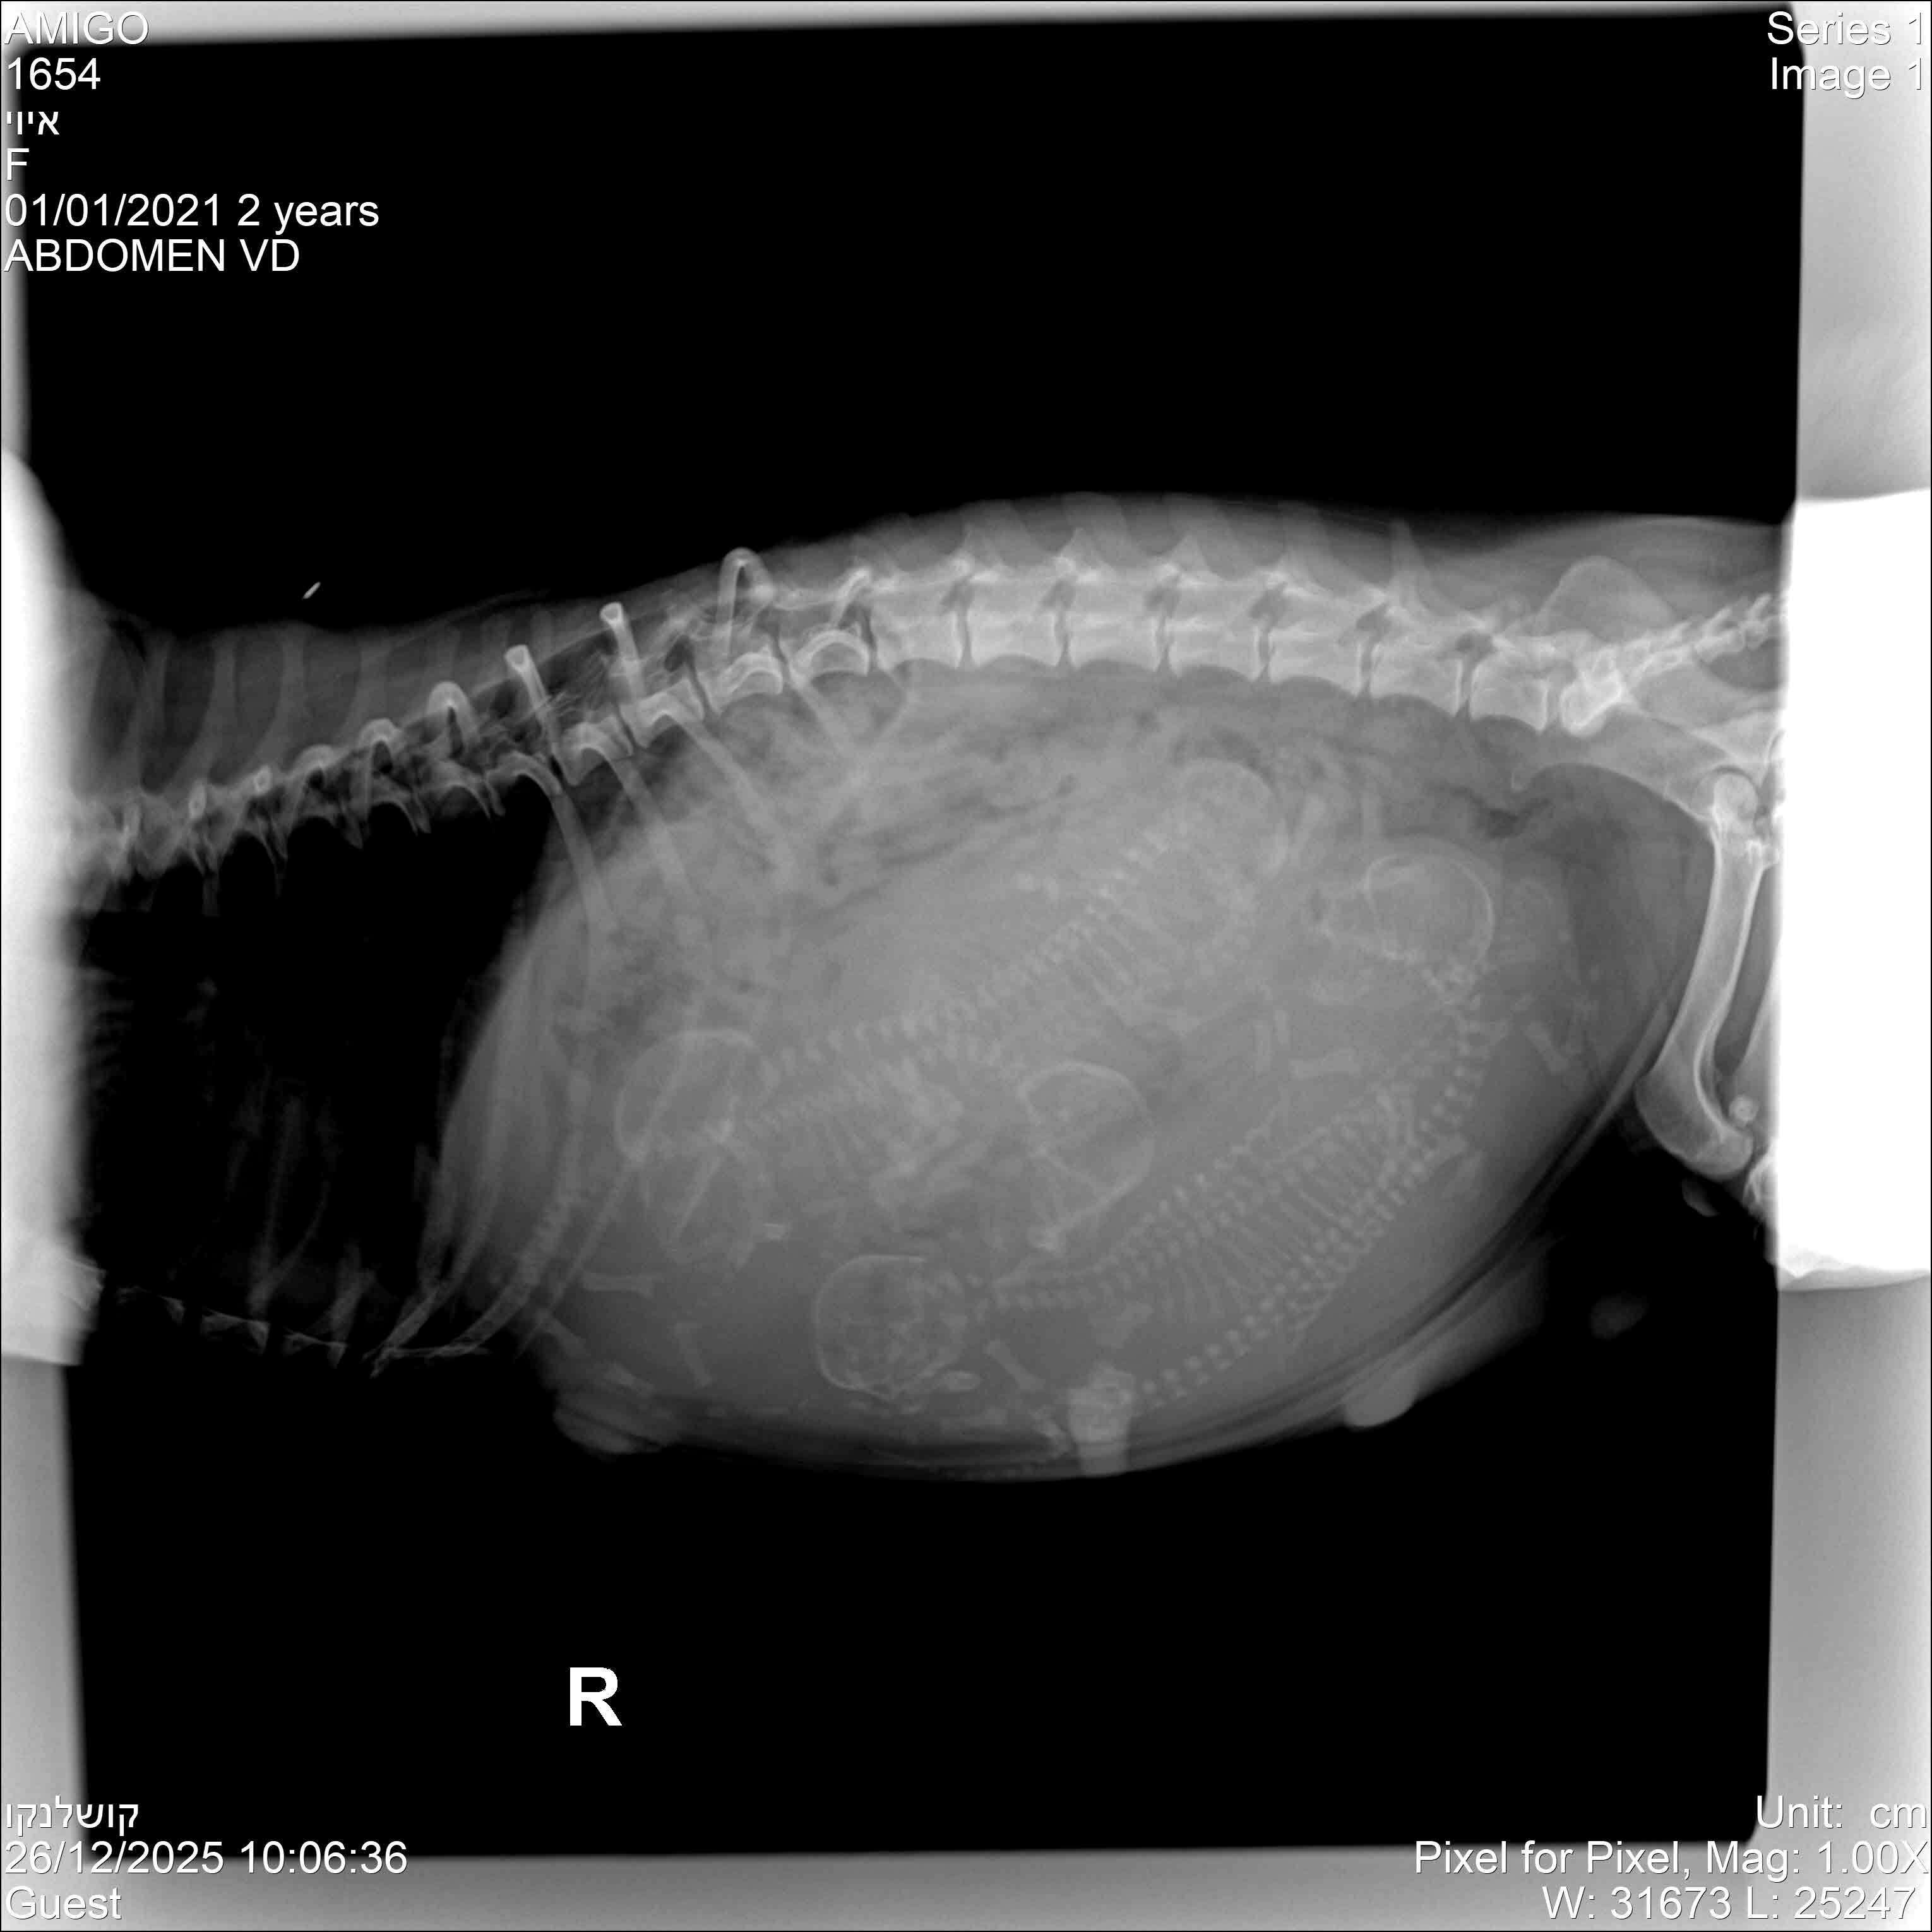

Кстати, в пятницу мы сделали ей рентген - на снимке я увидела 6 щенков. Мнения тех, кому я показала это фото, разошлись от 5 до 8 щенков, но большинство всё же склоняются к шести.